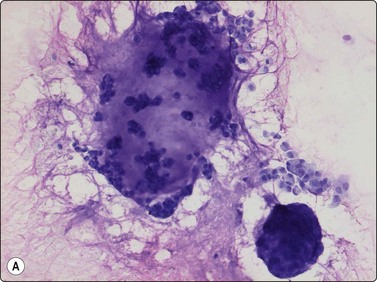

Alveolar rhabdomyosarcoma is a typical small round cell malignancy in FNB smears (Fig. 15.41). Smears show predominantly single cells, and stripped nuclei are common. Alveolar or rosette-like structures may be seen. The cells are mainly uniform with rounded or irregular nuclei and scanty cytoplasm. In almost every case, small rounded or pear-shaped cells with eccentric nuclei and eosinophilic cytoplasm are found (Fig. 15.42). The chromatin is variably coarse and nucleoli may be prominent. The multinucleated cells with small, dark nuclei, commonly seen in histologic sections are, in our experience, not a common finding in smears (Fig. 15.43).

image

Fig. 15.41 Alveolar rhabdomyosarcoma

The cells are mainly uniform with rounded or irregular nuclei and scanty cytoplasm (H&E, IP).

Fig. 15.42 Alveolar rhabdomyosarcoma

In almost every case, small rounded or pear-shaped cells with eccentric nuclei and eosinophilic cytoplasm (small rhabdomyoblasts) are found (H&E, HP).